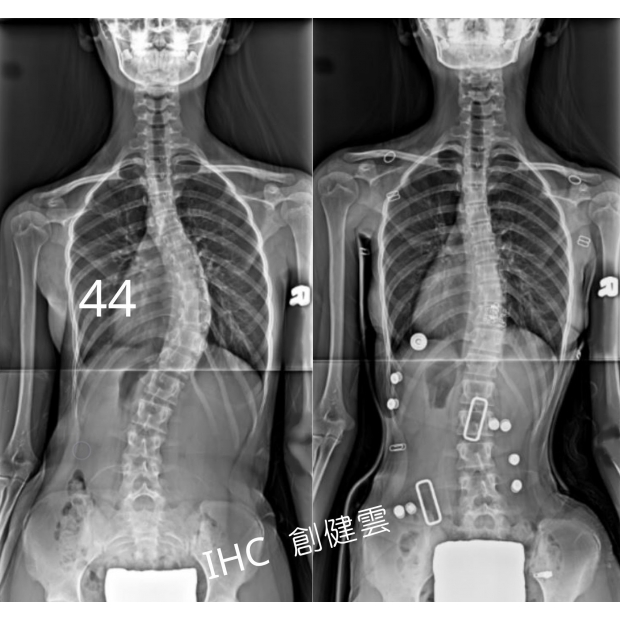

15歲重度脊椎側彎女孩

胸彎44度